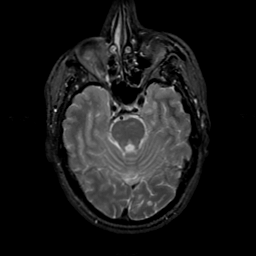

MR Study #22, December 1, 1991 -- Slice #16